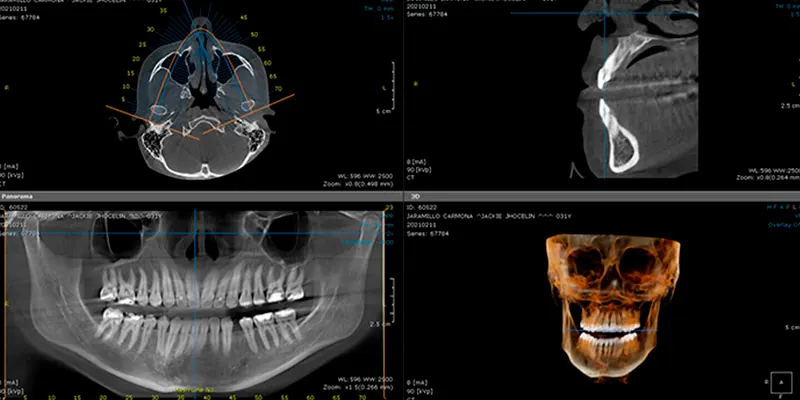

Es una técnica avanzada que nos permite obtener imágenes tridimensionales detalladas de tus dientes, huesos y tejidos faciales. Esta tecnología nos proporciona una visión más completa y precisa de su estructura dental y es especialmente útil en la planificación de implantes dentales, cirugía ortognática y otros procedimientos complejos.